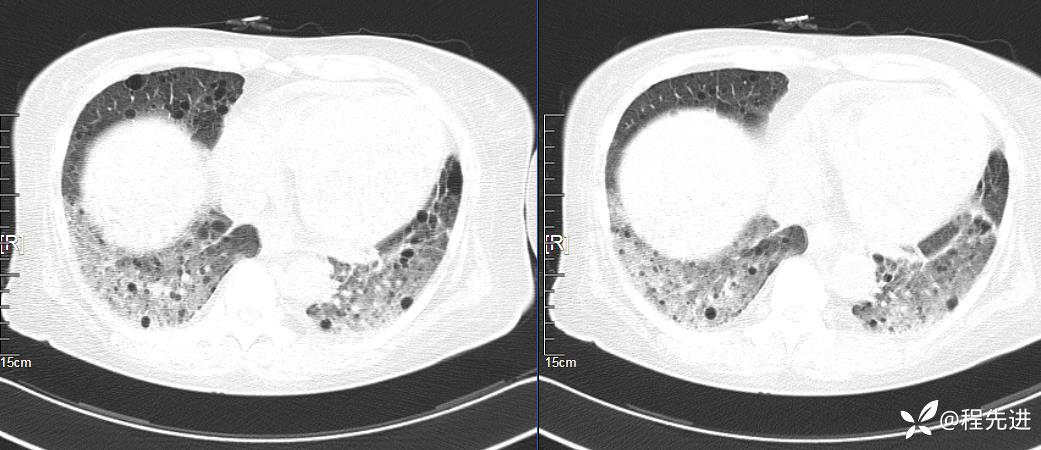

简要病史:胸闷、气促、进行性呼吸困难5年,双下肢浮肿、恶心呕吐1周

CT平扫(纵隔窗无特殊,就不上传了):

1、两肺弥漫性肺气囊的鉴别诊断有哪些?

2、本例肺气囊分布有什么特点?肺气囊有无小叶核心?有没有间质纤维化及伴发结节?